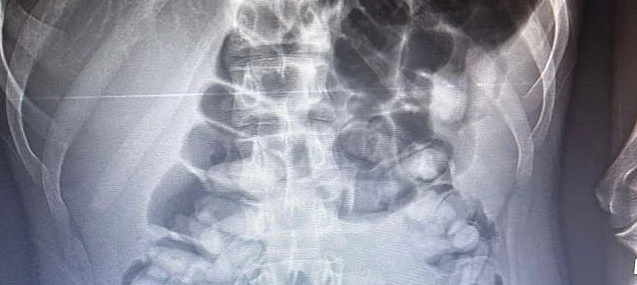

Erzurum Emniyet Müdürlüğünden konuya ilişkin yapılan açıklamada,” Uyuşturucu madde ticareti ve sevkiyatına yönelik yapılan çalışmalar neticesinde 13.11.2023 tarihinde tespit edilen yolcu otobüsünde durumundan şüphelenilerek uyuşturucu madde yutmuş olabileceği değerlendirilen ve İlimiz Şehir Hastanesinde iç beden muayenesi yaptırılan S.A. (2006 doğumlu) isimli şahıstan toplam 1 kg 134 gram Afyon Sakızı maddesi ele geçirilmiş, konuyla ilgili adli mercilere sevk edilen şahıs tutuklanarak cezaevine teslim edilmiştir. Uyuşturucu veya uyarıcı madde satışı, kullanımı ve nakli ile ilgili mücadelemiz kararlılıkla sürdürülecektir.” İfadelerine yer verildi.